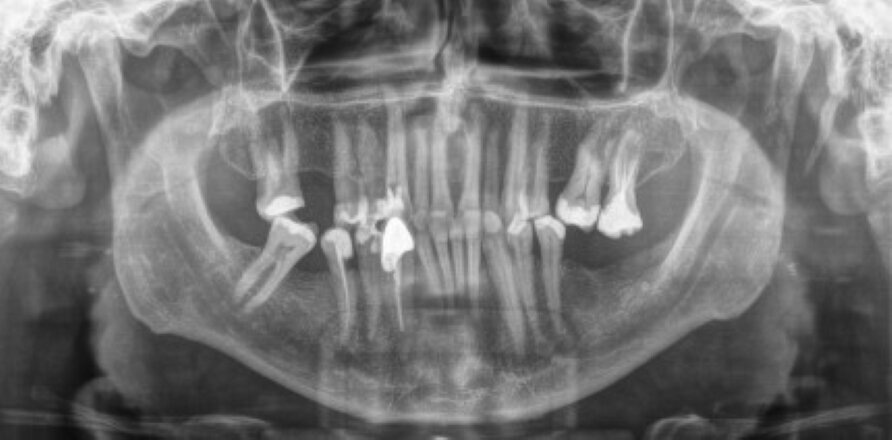

Da je zub poseban zbog svoje dužine moglo se videti već na OPT snimku, mada je „to bilo iznenađenje s obzirom na stas pacijenta“, rekao je dr Lukas.

Ovaj zub je dr Lukas ekstrahovao još u proleće ove godine i to nije bila obična rutinska procedura, izjavio je dr Lukas: „Ovaj zub je zbog dužine morao da se odstrani operativnim putem. S obzirom da je zub već bio trepaniran sa palatinalne strane i da je koren bio veoma dugačak moralo se pristupiti zahvatu veoma oprezno da ne bi došlo do frakture korena što bi zakomplikovalo proceduru.“

Dosadašnji rekorder u dužini ljudskog zuba bio je čovek iz Indije. Međutim, zub koji je izvadio dr Maks Lukas (Dr. Max Lukas), nemački stomatolog iz Ofenbaha na Majni, dužine 37,2 mm postao je novi rekorder jer je dužina tog zuba za 0,5mm veća od dosadašnjeg „rekordera“.